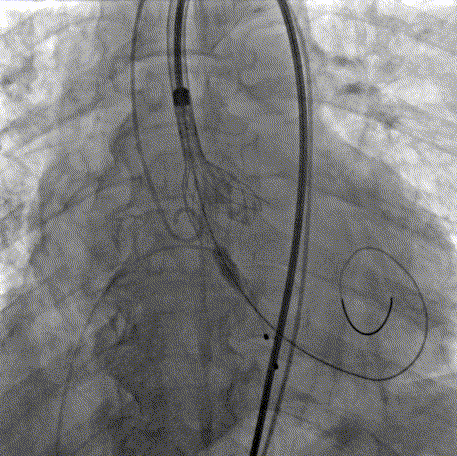

手术过程

术前主动脉根部造影

20mm球囊预扩

AV26瓣膜定位

AV26瓣膜工作位造影

AV26瓣膜释放

术后主动脉根部造影

本例手术为重度钙化二叶式病变重度主动脉瓣狭窄TAVR手术,团块状钙化挤压存在移位瓣周漏风险,术前手术团队对患者进行了全面细致的评估,确定假体瓣膜锚定区域范围,制定术前释放策略。何柳平主任团队通力配合、精准释放,充分利用TaurusElite可回收功能,在瓣膜释放至2/3时,多角度评估瓣膜植入深度、锚定力以及冠脉灌注情况,确认瓣膜植入深度合适、锚定力稳定,缓慢逐个脱钩,进行瓣膜释放。释放后造影显示瓣膜膨胀良好,行血流动力学评估,跨瓣压差从术前100mmHg降至15mmHg,少量瓣周漏,手术圆满完成。